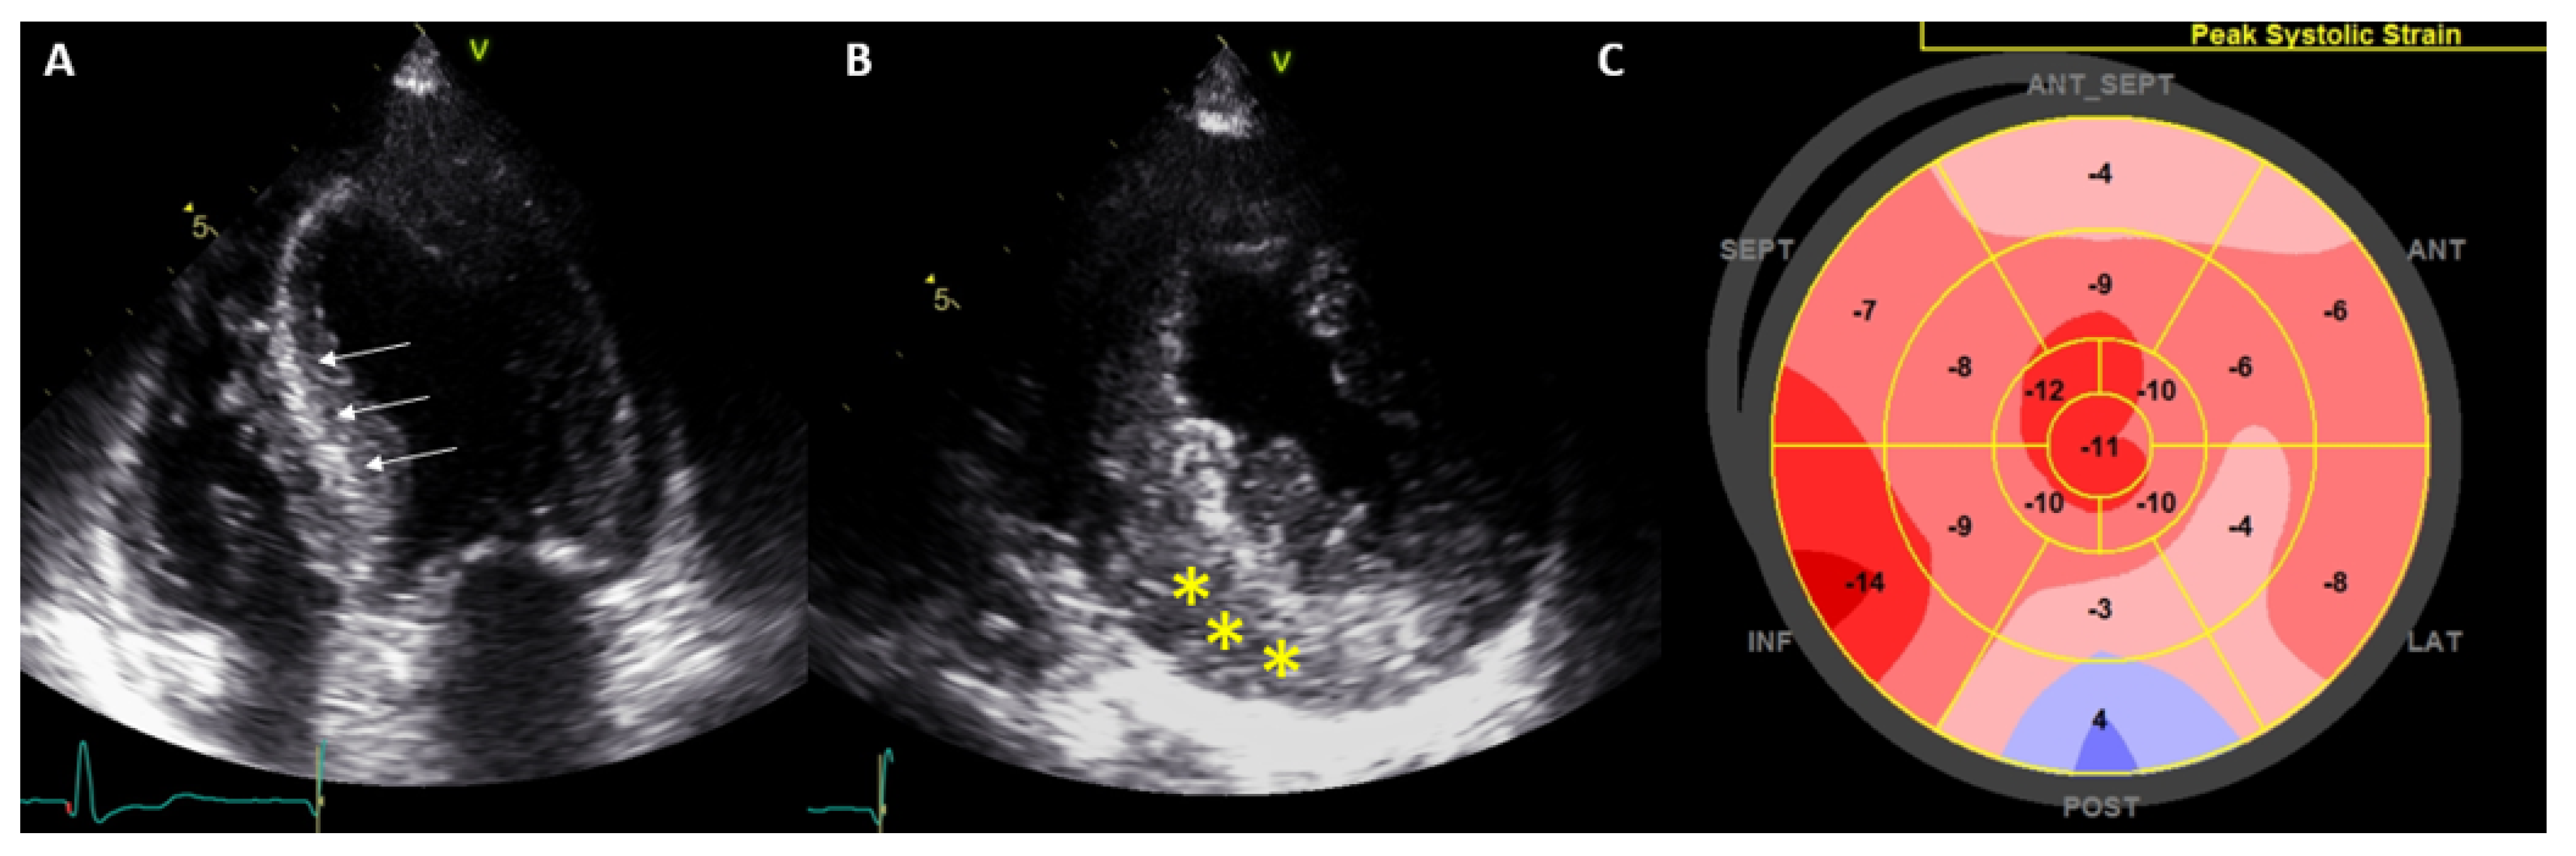

4.2. Cardiac Amyloidosis

4.3. Fabry Disease